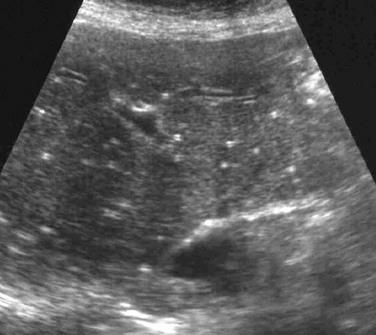

Fatty infiltration

Fat Sparing

- diabetes mellitus

- obesity

- alcohol abuse

- exogenous steroids

- drugs (amiodarone, methotrexate, chemotherapy)

- IV hyperalimentation

focal fatty infiltration